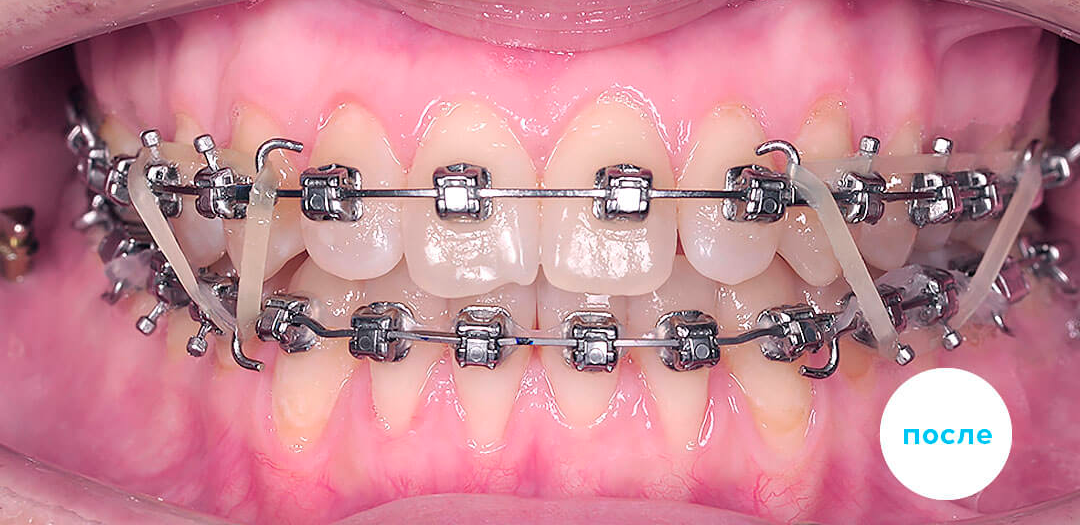

Работы специалиста